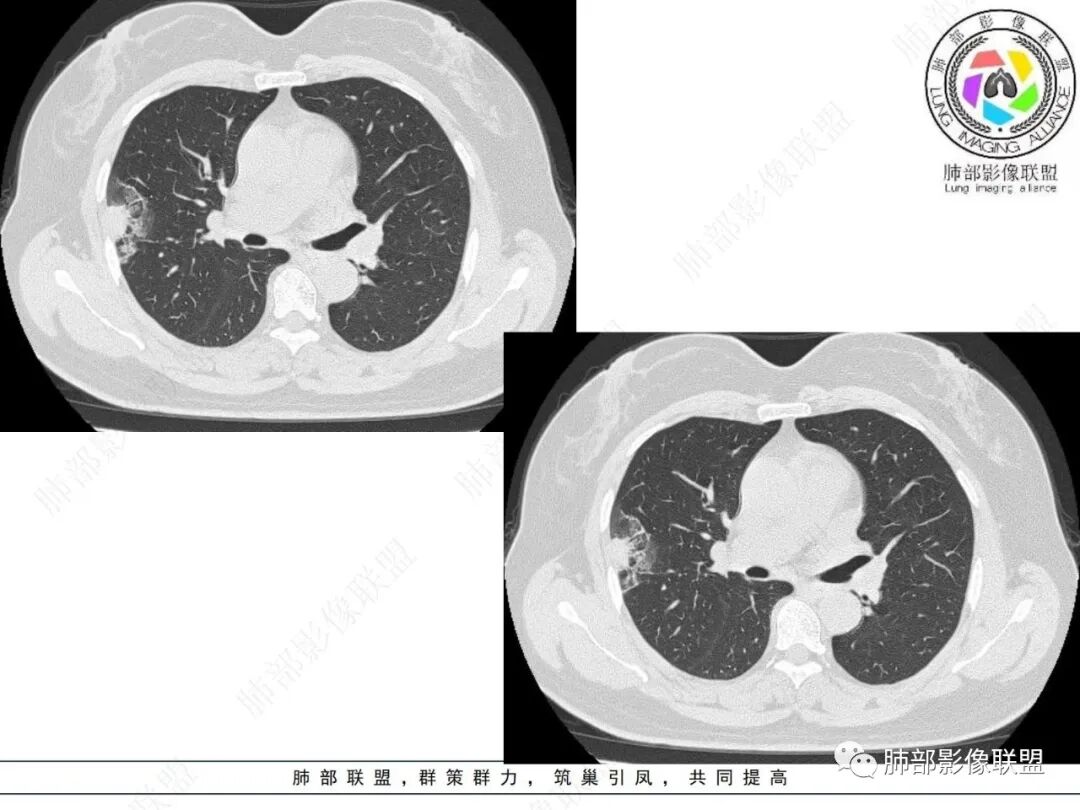

2.影像特点:

右肺上叶胸膜下混合磨玻璃团片影。

周围磨玻璃部分间杂条索状高密度区,密度欠均匀(可疑重力分布趋势),其磨玻璃影边界大多较清楚或可分辨,部分“L型”边缘,提示小叶间隔阻挡可能。血管穿行自如,可疑远端支气管进入。

实性部分较密实,不规则,隐约见棘突或刺状突起,未见钙化、空洞或液化区,实性边缘可见斑状略低密度间隙(借用王兆宇老师课件,称其呈“松软”的形态)。动脉期实性部分较明显不均匀强化,如果有完整增强图,还可以观察内部血管情况。

纵隔窗相对肺窗病灶相对小,仅部分实性影呈现。病灶张力不高,相邻胸膜增厚(糊墙),未见明显胸膜牵拉凹陷。

未见卫星病灶,远处未见磨玻璃结节影。

双肺门及纵隔未见明显增大淋巴结。心包及胸腔未见积液。

右肺上叶胸膜下混合磨玻璃结节,磨玻璃部分与实性部分密度都不均匀,病灶有重力分布效应,小叶间隔阻挡,收缩力羸弱。中老年女性,如此大范围病灶,缺乏临床表现,会让人警惕非感染性病变,尤其是恶性病灶可能!

病灶磨玻璃部分边界较清楚,有重力分布趋势,可能会想到黏液腺癌,或者分泌粘液的腺癌的可能性。不支持地方也有,如实性部分密度偏高,病灶强化程度偏高等。